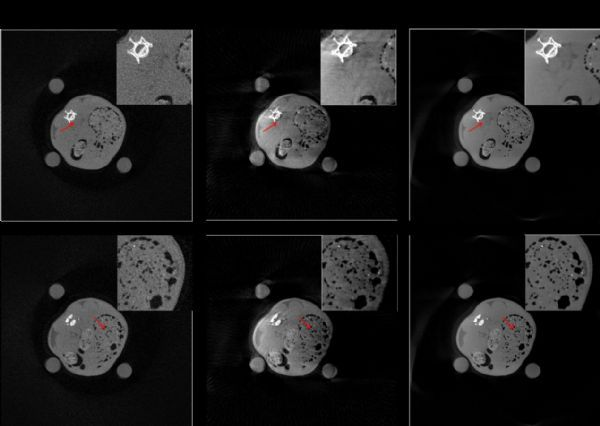

中国科学院苏州生物医学工程技术研究所医学影像室X射线组的李铭等人提出了基于SL0的正则化函数模型,该模型根据重建图像的噪声性质,自适应调整正则化约束强弱,从而取得较好的噪声抑制和软组织保护特性。该方法在仿真实验、临床数据实验及动物数据重建中均能取得较为理想的重建结果。